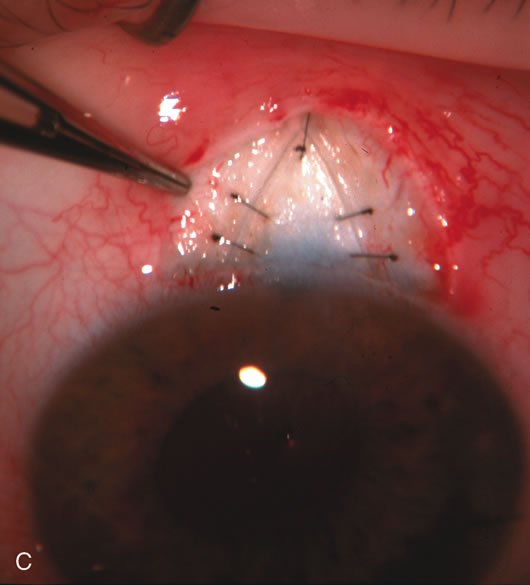

During preoperative slit-lamp biomicroscopy, the surgeon evaluates the condition of the conjunctiva and decides on a fornix-based or a limbus-based conjunctival approach.174–177 There are definite advantages and disadvantages of each approach (Table 3). With proper wound construction, there appears to be very little difference in long-term IOP control between the two incisional groups. However, the long-term bleb appearance varies considerably between the two incisional groups,178 with a limbus-based conjunctival flap more likely to develop a cystic bleb especially if an antimetabolite is used179 (Fig. 8).

Fig. 8. Bleb appearance after limbus-based versus fornix-based conjunctival flaps. Even though the IOP is thought to be equivalent between limbus and fornix-based conjunctival flaps, the final bleb appearance varies considerably. A. During a limbus-based approach, an incision through conjunctiva 10 mm posterior to limbus will sever through multiple arterial vessels, increasing the likelihood of an avascular bleb. B. The tissues are dissected down to the sclera further cutting feeder vessels from Tenon's capsule. C. The wound is closed inciting a cascade of wound healing events that may ultimately lead to scarring producing a barrier to aqueous flow. D. This leads to walling off of a bleb that has lost some of its overlying vascularity (pale cystic avascular bleb). E. During a fornix-based conjunctival approach, the incision is made at the limbus and tissues undermined. F. The incision is closed at the limbus; no conjunctival vessels are severed over the bleb area. G. This fosters the formation of a shallow diffuse pale bleb with a normal vessel pattern.